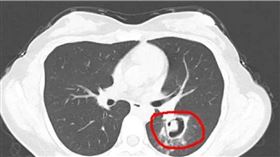

她肺部長「小樹芽」!醫化驗傻眼:發霉了

中國杭州1名王姓女子在1個月前,發現家具上發霉,便開...